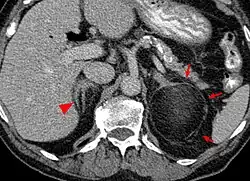

Pathologie

Myelolipome sind gelbe bis bräunliche, wenige Millimeter bis 30 cm große, umschriebene, jedoch nicht gekapselte Tumoren. Sie treten üblicherweise solitär und einseitig im Bereich einer Nebenniere auf, werden selten jedoch auch bilateral und/oder außerhalb der Nebenniere (z. B. im Retroperitoneum, Mediastinum, der Leber, in Muskelfaszien) gefunden. Mikroskopisch setzt sich der Tumor aus reifem Fettgewebe und myeloiden Zellen zusammen. Gelegentlich werden Infarktareale, Einblutungen oder knöcherne Metaplasien beobachtet.[1][2]

Die Mehrzahl der Myelolipome sind asymptomatisch und werden zufällig, etwa im Rahmen radiologischer Untersuchungen oder einer Obduktion gefunden. Nur gelegentlich, insbesondere bei größeren Tumoren, berichten betroffene Patienten von Bauch- oder Flankenschmerz. Selten bestehen endokrine Störungen wie das Cushing-, Conn-Syndrom oder eine angeborene Nebennierenhyperplasie.[1]